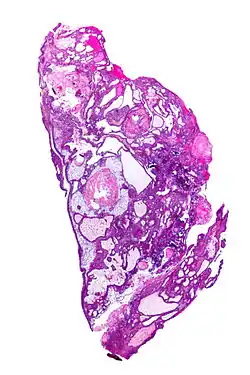

![]() Micrografía de un craneofaringioma (adamantinomatoso). Tinción HPS. | ||

El patrón histológico consiste en epitelio escamoso anidado rodeado por células organizadas radialmente. Es con frecuencia acompañado de depósitos de calcio y puede tener arquitectura papilar microscópica. Dos tipos diferentes son reconocidos:[7][8]

- El craneofaringioma adamantinomatoso, el cual se parece a los adamantinomas, el tipo más común de tumor dental, es caracterizado por la activación de mutaciones de CTNNB1; y,

- Los craneofaringiomas papilares son caracterizados por mutaciones de BRFAFv600e.[9]

- En el tipo adamantinomatoso, las calcificaciones son visibles en las neuroimágenes y son útiles en el diagnóstico, el tipo papilar raramente se calcifica.

En el examen macroscópico, los craneofaringiomas son quísticos o parcialmente quísticos con áreas sólidas. En el microscopio de luz, los quistes son vistos como revestidos por un epitelio escamoso estratificado. Perlas de queratina también se pueden ver. Los quistes están llenos usualmente con un fluido viscoso y amarillo, el cual es rico en cristales de colesterol. de una larga lista de posibles síntomas, las presentaciones más comunes incluyen: cefalea, retraso del crecimiento y hemianopsia bitemporal.